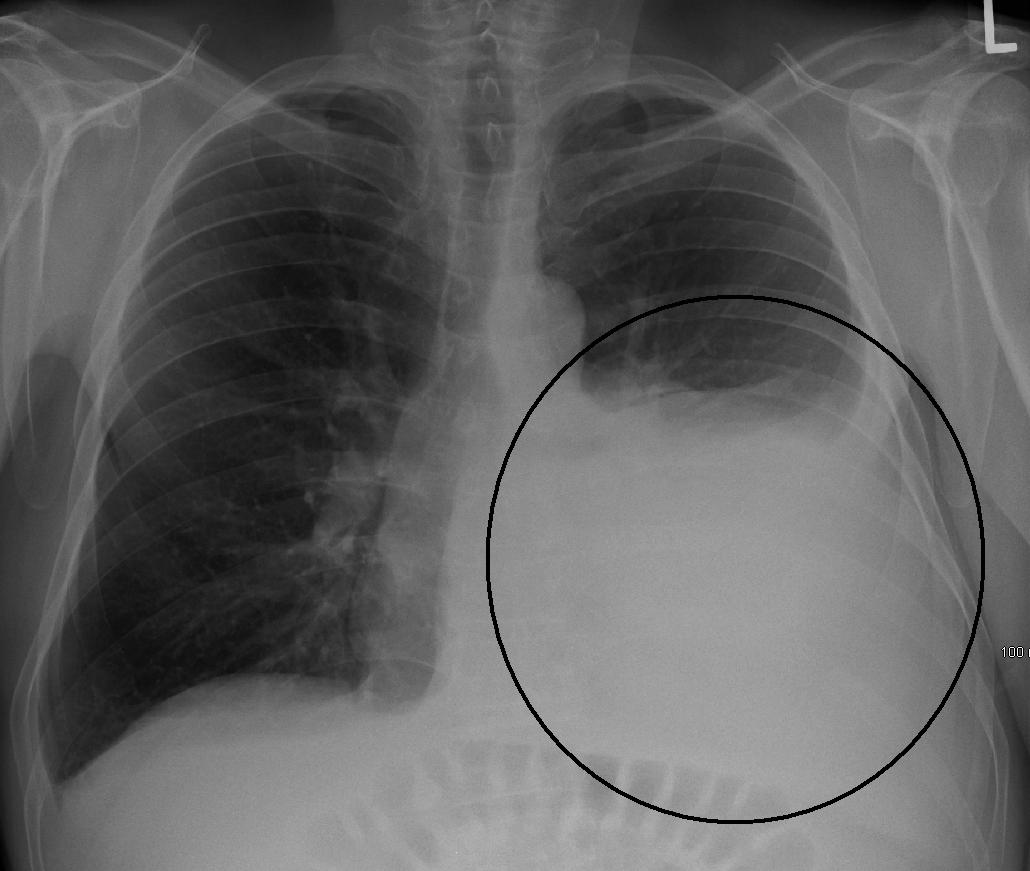

From atlas.mudr.org

Radiology case Pleural effusion Can Pleural Effusion Go Away The outlook or prognosis varies depending on what caused your pleural effusion and what other conditions you have. Pleural effusion, sometimes called water on the lung, is a buildup of fluid between the lungs and the chest cavity. Pleural effusions are diagnosed in about 1.5 million individuals in the united states annually [1]. Among the causes, pleural infection,. A thin. Can Pleural Effusion Go Away.